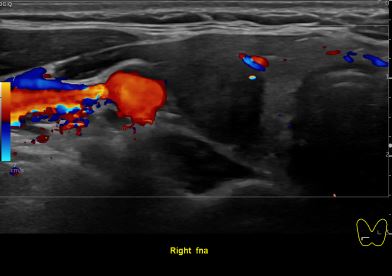

상기환자 외부건진 이상소견으로 세침검사위해 내원하신 30대후반 여성분으로

의심스러운 갑상선 우엽 세포검사후 갑상선암으로 진단되었습니다